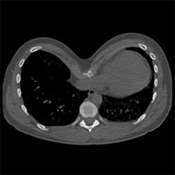

Cálculo del índice de Haller de un Pectus

El índice de Haller se estableció en 1987 para evaluar la importancia de un Pectus a partir de un cálculo realizado en una imagen digital. Se calcula a partir de un corte de escáner en el punto más profundo de la depresión: es la relación entre el ancho y la profundidad máxima.

Permite medir la profundidad del Pectus Excavatum con mayor precisión, particularmente en mujeres donde la deformación es difícil de evaluar debido al volumen mamario. Cuanto más alto es el índice de Haller, más profundo es el Pectus Excavatum

Es práctico y sigue siendo utilizado, pero proporciona una idea imperfecta de la importancia de la depresión y no predice ningún posible y raro impacto funcional del pectus.